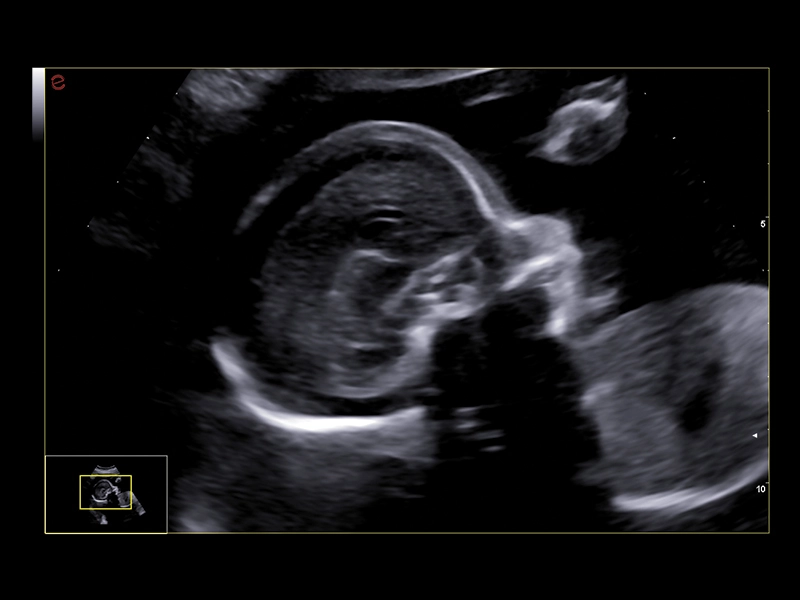

MyLab™C25 - Baby face

MyLab™C25 - Baby face